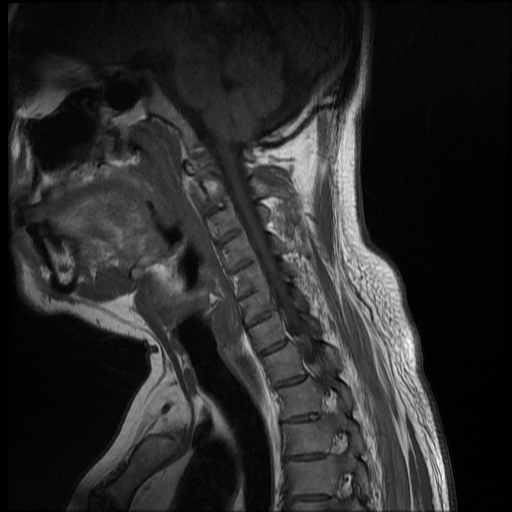

Se observa perdida de la lordosis normal de la columna cervical.

Se observa hipo intensidad del ligamento longitudinal anterior y posterior de la columna cervical, también se observa perdida de la movilidad y rigidez de la misma, los ligamentos interespinosos se ven hipointensos en T2 y en T1, al igual que el pliegue nucal, lo que sugiere calcificación de estas estructuras anatómicas.

Se observa fusión de las vertebras cervicales 5-6 y 6-7, dando la apariencia de bambú.

• Perdida de la lordosis

• Ligamentos espinales anterior, posterior, interespinosos y pliegue nucal calcificados

• Fusión de vertebras cervicales 5-6 y 6-7.